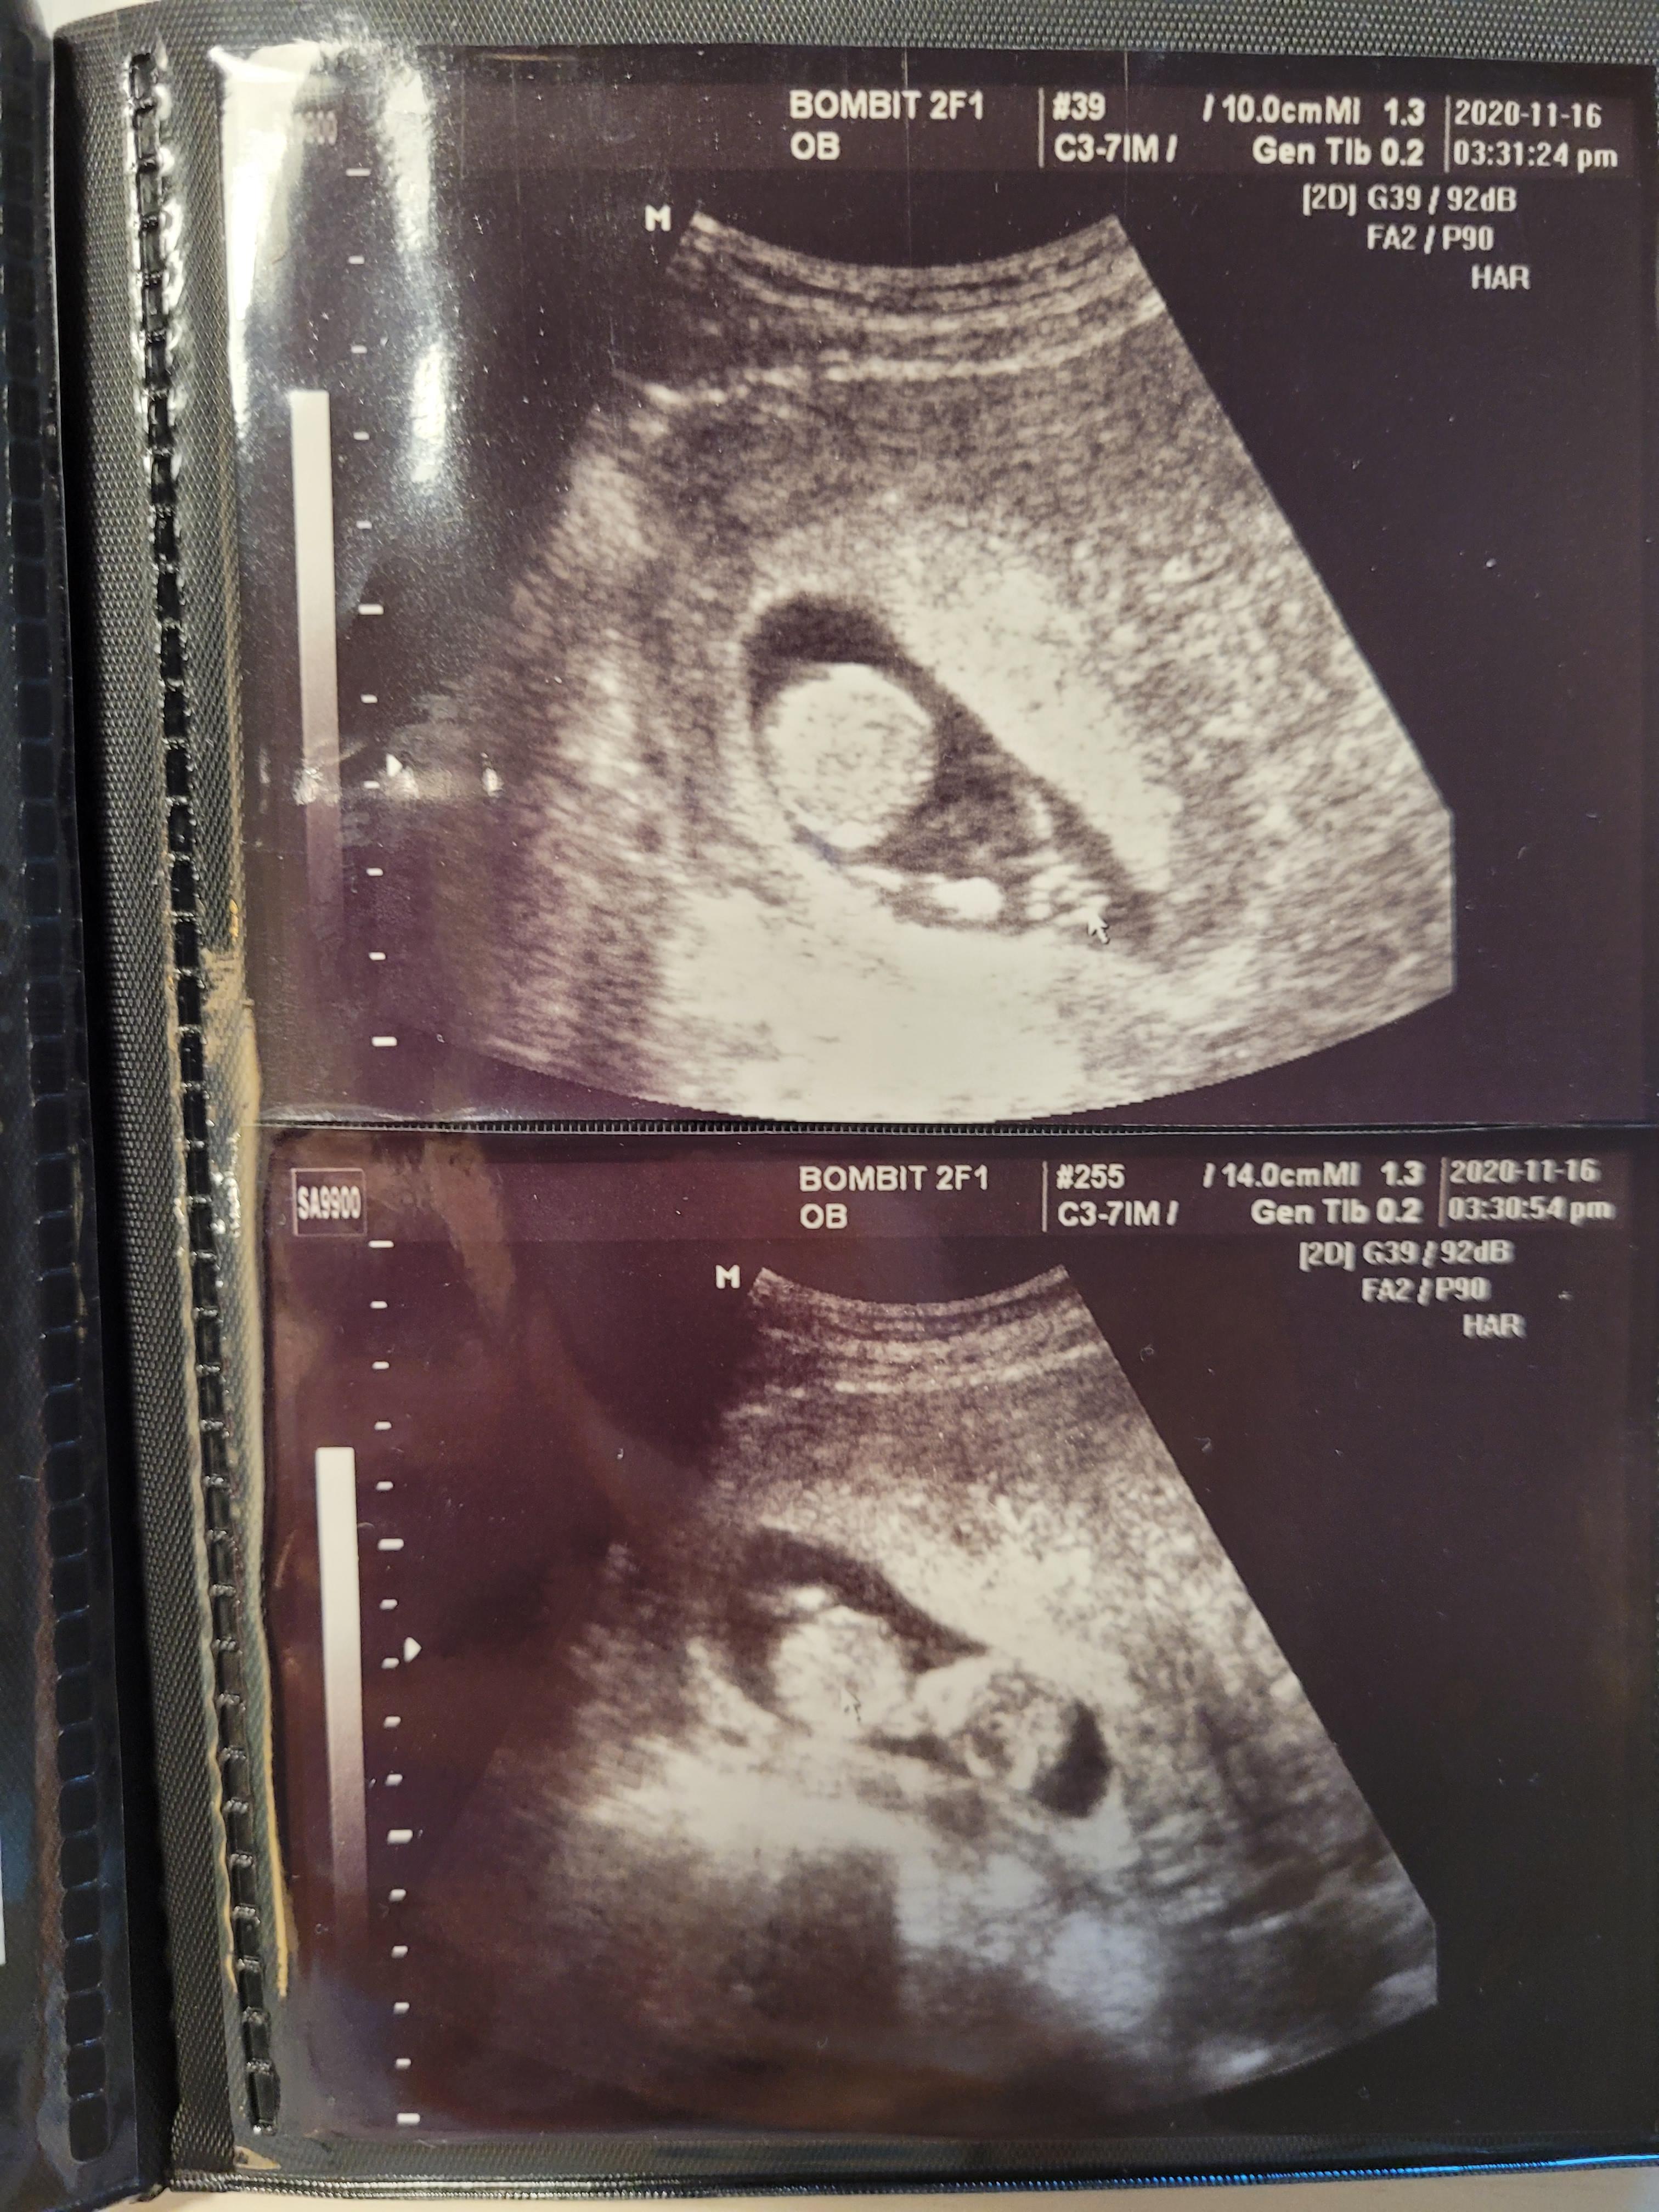

입체초음파를 보고, 다시 진료실에와서 주치의 원장님과 다시 초음파검사를 했어요.

넘넘 귀여운 아가^^

꼬물꼬물 너무 잘움직이고 귀엽더라고요.

산전검사는 보건소에서 했던 산전검사 결과지를 보시고, 더 필요한 검사만 추가로 진행하기로 했어요.

채혈을 해야하는데 16주에 어차피 채혈을하니까 그때 같이 검사하기로 했고요.

보건소에서 받은 기형아검사쿠폰으로 결재해서 조금 할인된 금액으로 검사를 받았습니다.

안양 거주하시는 분들은 쿠폰 꼭 챙기세요^^